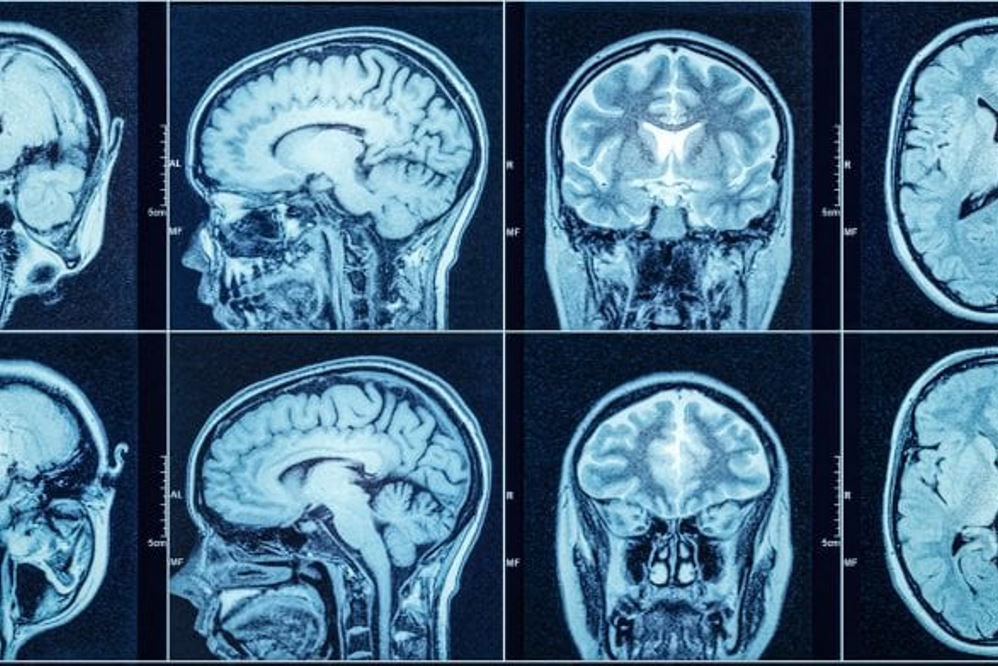

Uitwisseling tussen hersengebieden minstens zo belangrijk als gebieden zelf

09-11-2022 Het zijn niet de individuele hersengebieden, maar de verbindingen ertussen die ertoe doen: neurowetenschappers zijn met een nieuw model gekomen dat beschrijft hoe ons brein werkt. Aan de hand van dit nieuwe model kunnen we beter begrijpen waarom en hoe onze hersenen van mens tot mens verschillen. De…